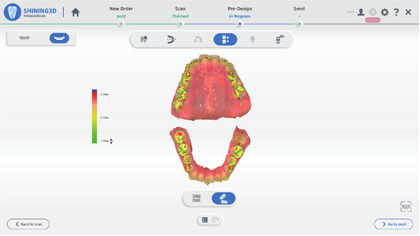

智能掃描

掃描更流暢

軟件智能識別并擯除頰舌側等雜余數據,實時數據干凈清晰無 干擾,口掃更加快速準確。

0.01mm

準中更準

優化軟件算法及硬件成像機制,Aoralscan 3精度優化超過30%,與模型掃描儀精度比對?≤0.01mm.*

正畸模擬

效果預覽 完美預定

智能識別自動分牙、排牙

口掃數據直接輸出正畸模擬

生成二維碼分享

口掃數據直接輸出正畸模擬

生成二維碼分享

口腔健康檢查3D報告

了解更多,參與更多,滿意更多

病例報告包括齲齒、牙缺失、牙結石、色素等

標準化接診療程,便于病例追蹤及分析

生成二維碼分享查看